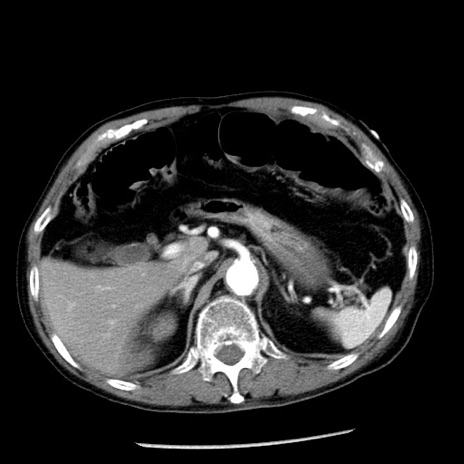

冠状断像

【症例】80歳代男性

【主訴】嘔吐

【現病歴】昨晩2回嘔吐あり、今朝になっても嘔吐あり。来院。

【既往歴】胃潰瘍

【身体所見】意識清明、BT 37.6℃、BP 166/95mmHg、HR 100bpm、SpO2 97%、腹部:平坦・軟、腸蠕動音聴取良好、圧痛なし。

【データ】WBC 21900、CRP 1.46